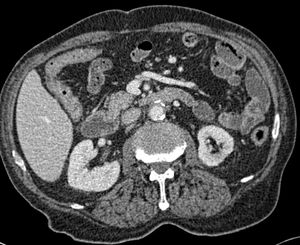

A 78-year-old man, with a significant past medical history of aortobifemoral bypass graft performed 6 years earlier, arrived at the emergency department with sudden-onset fever, chills, abdominal pain, and hematochezia. Abdominal CT imaging revealed soft tissue and fluid stranding around the proximal aortic graft, with tethering to the adjacent small bowel (fig. 1).